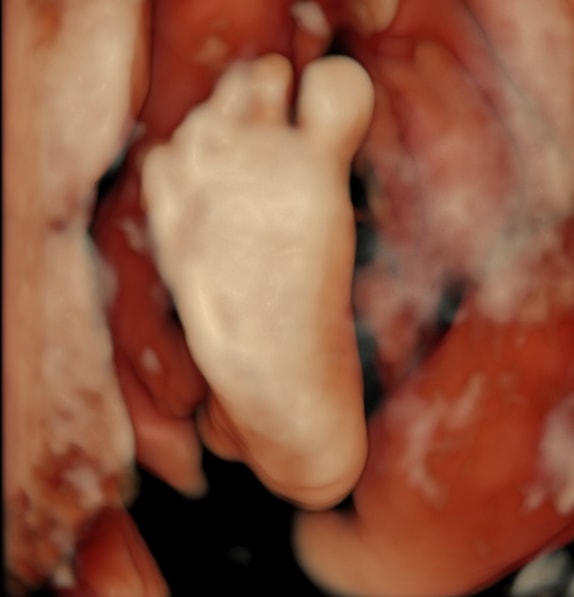

Tatiana, а зачем тогда пишут патологию, если могут написать, что не визуализируется? На хорошем оборудовании все очень четко видно, мне и стопы с пальчиками показали, и ладошки, и кулачки - можно сосчитать пальчики. Вот фотки 3д (делали просто для меня). Даже когда бесплатно делала, врач просила пойти погулять, поесть, чтоб малыш перевернулся, если не смогла что-то рассмотреть. В общем, странная история, слава богу все хорошо Изображение Изображение

Tatiana, вот где пальцы одной длины, это в Ставрополе делали на экспертнике, остальное Ростов, вот такие диагнозы мне ставили фото где все слиплось это в ПЦ смотрели, когда синдактилию поставили Последнее фото, узи за очень дорого в Ростове Я думаю, что давать оценку как видит врач не стоит, но в данном случае, я очень рада, что супер модный эксперт и спец в своем деле ошибся Изображение Изображение Изображение